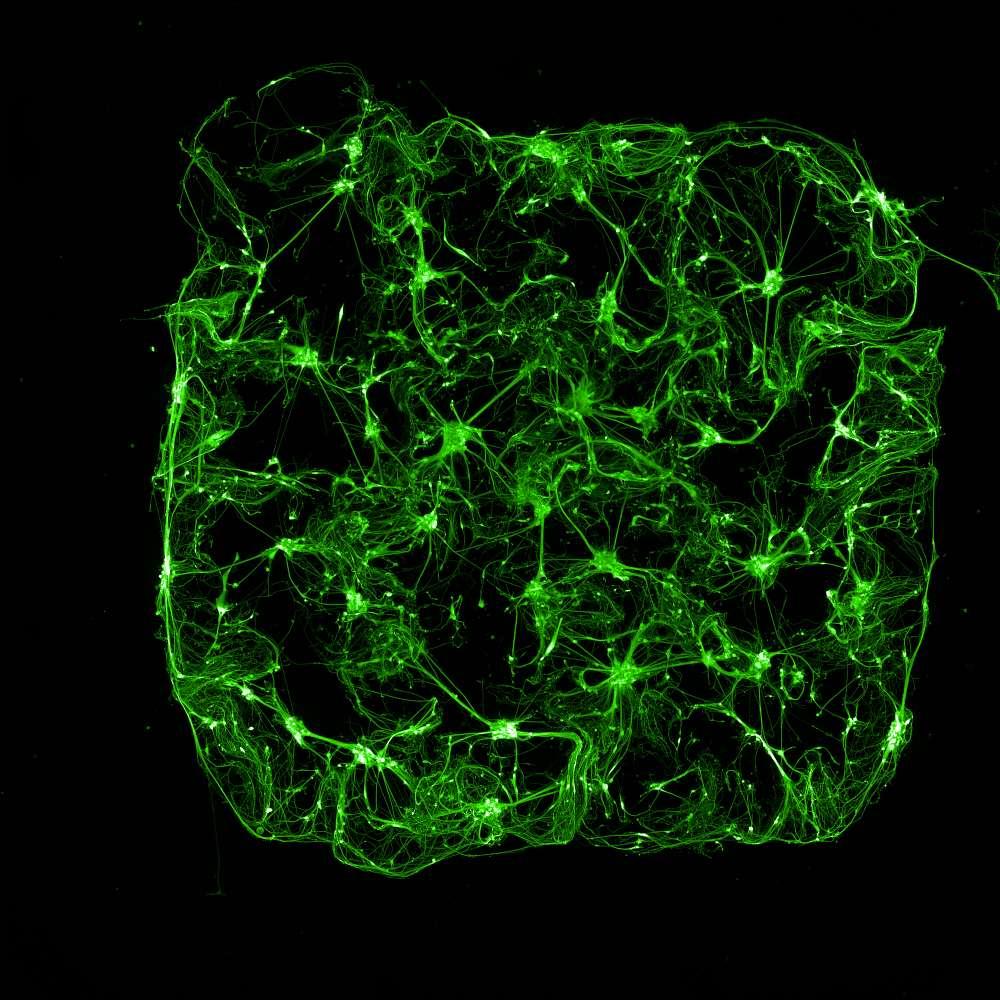

Calceinlabellingofneuron-astrocytecoculturesatmultipletimepointsshowedrobustcellviabilityandincreasedculturecomplexityovertime.

1week7weeks